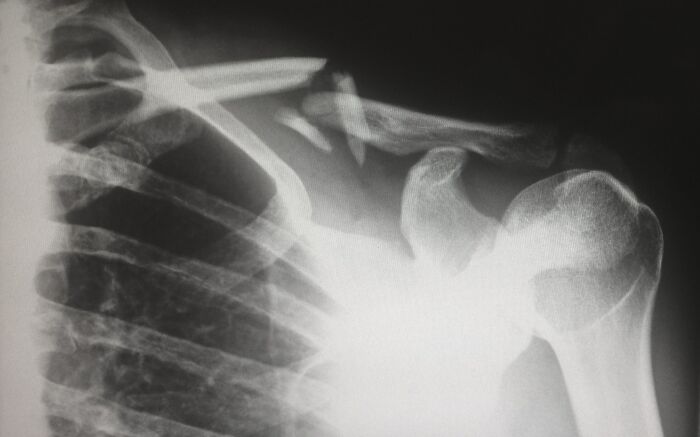

When X-ray technology first became widely available to pediatricians, they noticed a startling high number of broken bones. Befuddled doctors assumed there was a previously unknown pediatric bone disease being observed for the first time. Turns out we had no idea how common child abuse is.